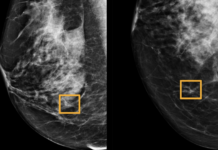

Google Health’s Artificial Intelligence better than radiologists at spotting breast cancer

An artificial intelligence program was developed by Google that outperforms clinical specialists in detecting breast cancer in mammograms, according to researchers.